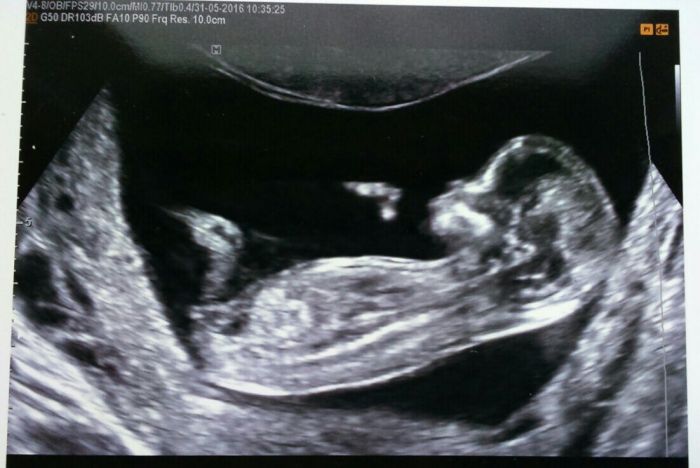

Ahoj holky, včera screeaning dopadl dobře. Riziko je jen kvuli věku,jinak paní doktorka kontrolovala všechny orgány a vše bylo v pořádku. Nosní kustka,projasnění šíje taky. Srdíčko tlouklo. Byli jsme tam skoro hodinu. Byla velmi pečlivá a milá. Akorát prutok jedné sévy nešlo moc změřit,mimi bylo špatně natočené, musela jsem jít běhat po schodech, ale stejně se otáčelo obráceně. Tak nám to trochu horší průměr. JIank zase říkali,že to vypadá na holčičku, ale potvrdí se to až později. Těhotenství 13+3 ..termín 3.prosinec

To je krasna fotka, takze nejspis princezna, slusi ji to

Julčo, nádherná fotečka. A super termín, to mám zrovna narozky.